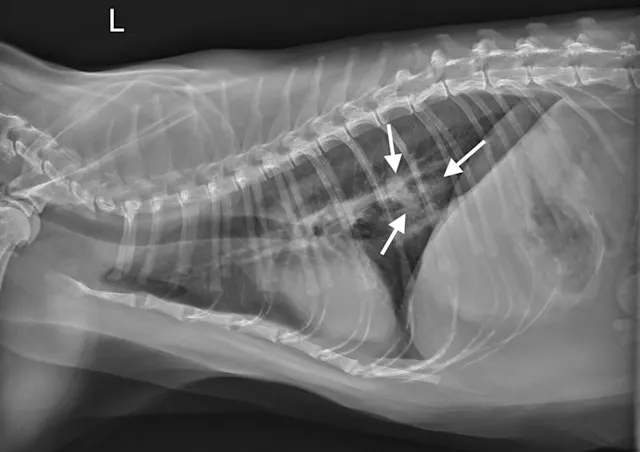

Figure 1A

Canine lung tumor

In these 3-view thoracic radiographs of an 8-year-old neutered male boxer with a lung tumor, a large soft tissue mass visibly extends to the lung lobe margins, nearly causing complete consolidation of the right middle lung lobe. Several closely spaced air bronchograms at the caudal margin of the mass are consistent with atelectasis caused by the expansile nature of the mass (Figure 1A; arrows). The apparent right mediastinal shift (ie, shifting of the cardiac silhouette to the right) in the ventrodorsal view (Figure 1C) is, at least in part, due to a moderate degree of patient rotation.

This patient underwent a right intercostal thoracotomy and lung lobectomy for tumor resection. On exposure of the thoracic cavity during surgery, it was found that the tumor was in contact with the right side of the heart, and, accordingly, occasional ventricular arrhythmias (ie, 3-4 per minute) were noted. A narrowly excised low-grade pulmonary carcinoma was confirmed via histopathology.